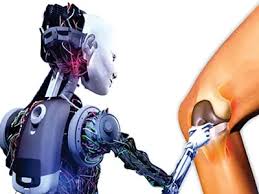

Introduction Robotic orthopedic surgery in Sukma is revolutionizing the way musculoskeletal conditions are treated. Today, joint disorders, injuries, and degenerative diseases are becoming increasingly common due to aging, lifestyle...

Introduction Robotic orthopedic surgery in Sakti is transforming the field of orthopedics by delivering unmatched precision, improved outcomes, and faster recovery. Today, orthopedic conditions such as joint degeneration, fractures,...

Introduction Robotic orthopedic surgery in Sarangarh-Bilaigarh is transforming the way complex bone and joint conditions are treated. Today, patients expect not only accurate diagnosis but also highly precise surgical...

Introduction Robotic orthopedic surgery in Rajnandgaon is transforming the way complex bone and joint procedures are performed. Today, patients not only expect effective treatment but also demand faster recovery...

Introduction Robotic orthopedic surgery in Raipur is rapidly transforming how surgeons treat complex bone and joint conditions. Today, patients not only expect effective treatment but also faster recovery and...

Introduction Robotic orthopedic surgery in Raigarh is revolutionizing the way complex bone and joint procedures are performed. With the integration of advanced robotic technology, orthopedic surgeries have become more...

Introduction Robotic orthopedic surgery in Narayanpur represents a major advancement in the field of orthopedic care, combining surgical expertise with cutting-edge technology to deliver highly precise and effective outcomes....